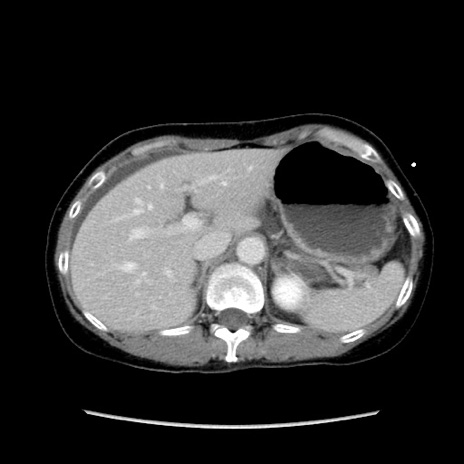

症例32(横断像)

【症例】40歳代 女性

【主訴】上腹部痛、嘔気・嘔吐

【現病歴】約9時間前頃から急に上腹部痛、嘔気、嘔吐が出現。改善しないため救急要請。

【既往歴】子宮頚癌(広汎子宮全摘術、放射線療法)、腸閉塞

【身体所見】腹部:平坦、軟、腸雑音亢進、上腹部を中心に腹部全体に圧痛あり。

【データ】WBC 8400、CRP 0.03